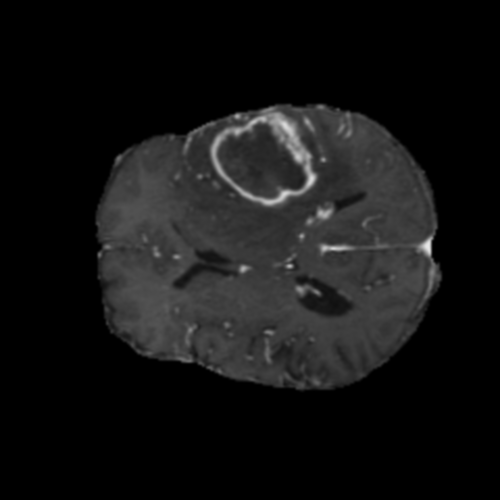

Ejemplos de Modalidades MRI

Visualización de las 4 modalidades de resonancia magnética y las segmentaciones de zonas tumorales utilizadas para entrenar el modelo

Glioma de Alto Grado (HGG)

Núcleo HGG

Núcleo

Edema HGG

Edema

Realce HGG

Realce

Tumor Completo HGG

Tumor Completo

Núcleo Edema Realce